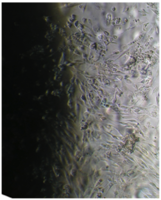

Исследование проведено на первичных культурах дермальных фибробластов и мезенхимальных стромальных клетках человека 4-12 пассажа.

Культуру дермальных фибробластов получали из кожно-мышечной ткани, а культуру мезенхимальных стромальных клеток – из фрагментов крыши черепа абортусов сроком 6-10 недель методом первичных эксплантатов (рис. 1, 2).

Клетки культивировали в стандартных условиях в термостате Sanyo – Incubator MIR-262 при температуре 37°С в среде МЕМ с 10% эмбриональной телячьей сыворотки в пластиковых культуральных флаконах Orange Scientific (производство Бельгии), Corning (производство США) площадью 25 и 75 кв. см. Тестирование производили в культуральных чашках Петри Sarstedt диаметром 3 см (рис. 3).

Вид монослоя и структура клеток не отличались от обычных в течение всех четырех суток наблюдения (рис. 32).

Это свидетельствует об умеренной стимуляции пролиферации фибробластов в культуре под влиянием недеминерализованной спонгиозы (таб. 9.).